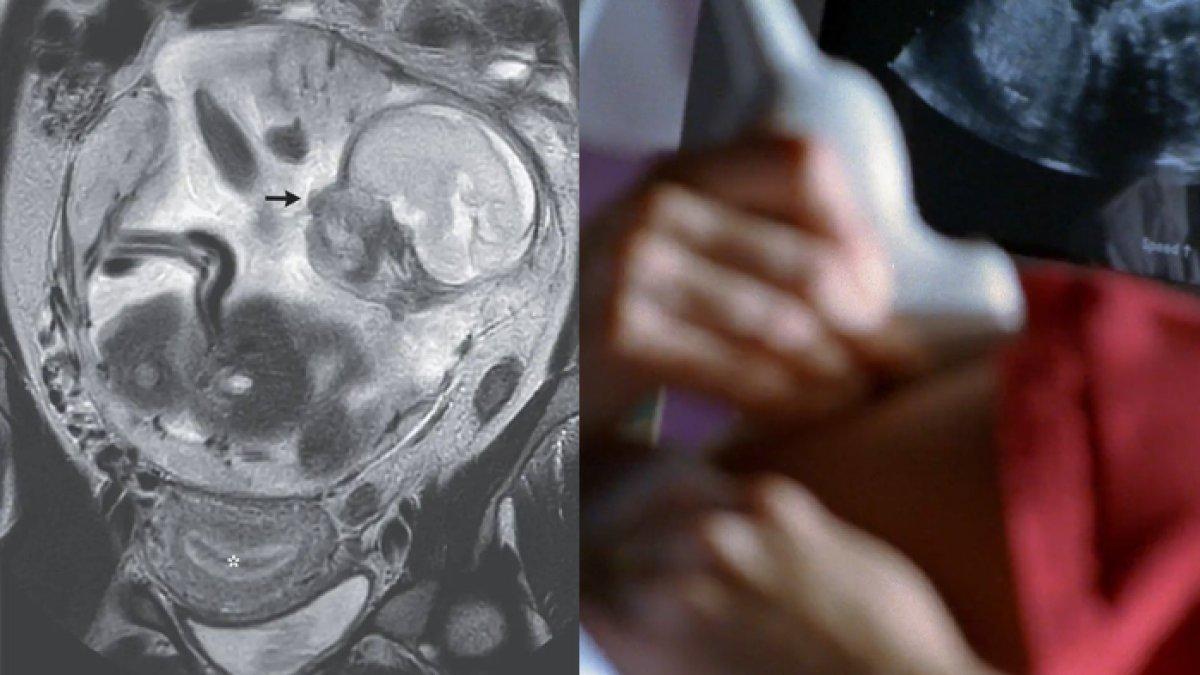

Wanita Syok, Periksa Sakit Perut Malah Dinyatakan Hamil, Tapi Tak Ada Bayi di Rahim, Kasus Langka

Seorang wanita syok ketika periksa ke dokter setelah mengeluh sakit perut, ternyata sedang hamil enam bulan

Bukan sakit perut biasa, dokter mengatakan wanita ini sedang hamil enam bulan.

Namun anehnya, bayi belum ada di dalam rahim wanita tersebut.

Dikutip dari Sanook, Senin (18/12/2023), seorang wanita pergi ke rumah sakit karena sakit perut dan secara tidak sengaja mengetahui bahwa dia hamil.

Namun tidak ada bayi di dalam rahim.

Menurut laporan Biro Laporan tersebut menyatakan bahwa seorang wanita berusia 37 tahun yang tinggal di pulau terpencil sempat sakit perut selama 10 hari, sehingga masuk IGD.

Sebelum menerima perawatan medis kali ini, ia sudah dua kali melahirkan dan mengalami satu kali keguguran.

Namun ia tidak pernah menderita penyakit menular seksual.

Selain itu juga tidak ada riwayat operasi

Sejak usia kehamilan 23 minggu, endometrium pasien mengalami penebalan.

Tapi tidak ada bayi normal di dalam rahim.

Karena bayi itu mempunyai tubuh "Biasa saja".